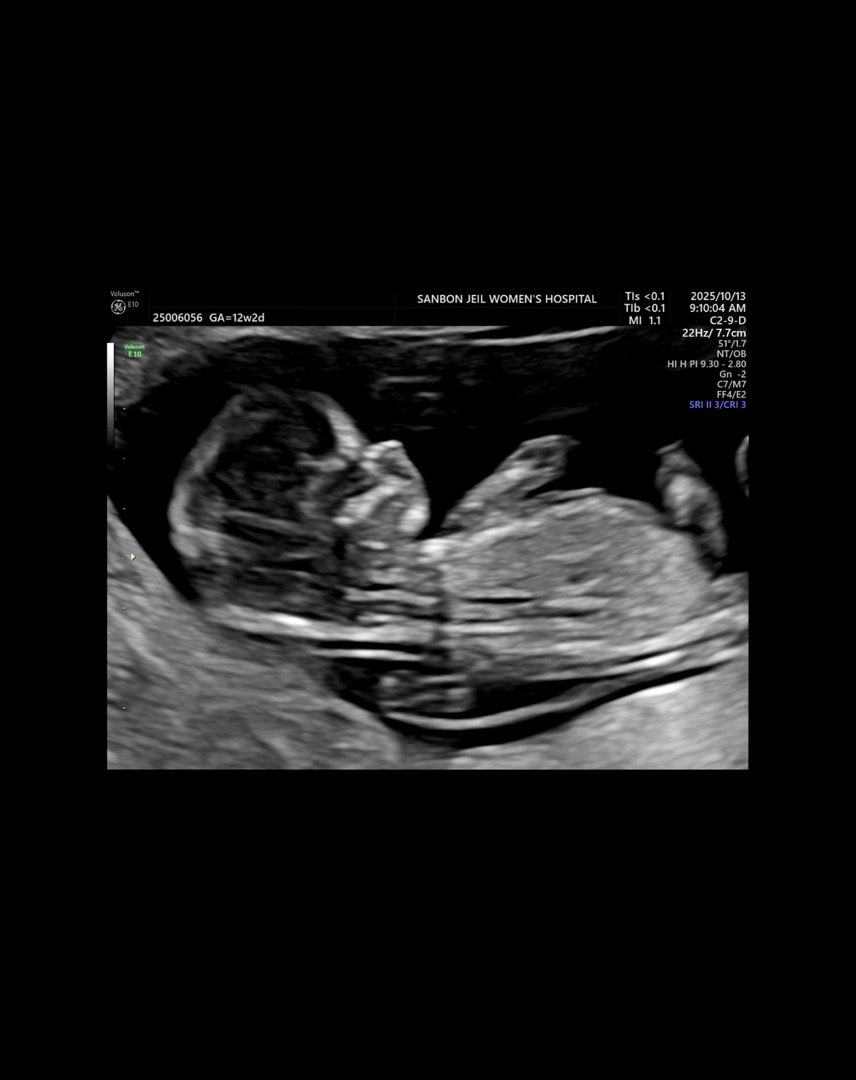

12주차 각도법 봐주세요옹💗

첫 아이라 성별이 궁금하네오 ㅎㅎㅎ 12w2d에 찍은 사진인데 각도법 봐주시면 감사드릴게요-!!!!